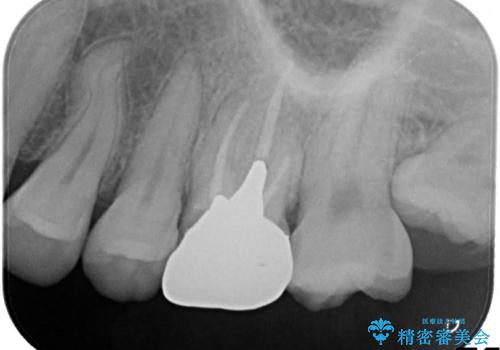

金属の奥歯 → 白い奥歯 根管治療からのやり直し

- 再根管治療→土台の築造 を行った上でのかぶせ物のやり替えをおこないました。

神経の無い歯のかぶせ物をやり替える際は、是非根管治療からしっかりやり直すことをおすすめします。